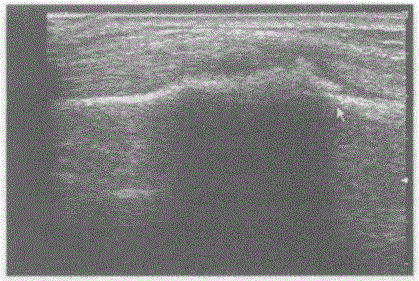

问题 临床资料:20岁,女,自述左腕部肿痛,发现肿物两月余。 超声综合描述:左腕部扫查骨皮质连续中断,呈虫蚀样,可见6.7cm×2.2cm不均质回声区,中部回声强,周边回声低,CDFI:内见伸入支血流信号。见下图及彩图123。 {图2} {图3} 超声提示: